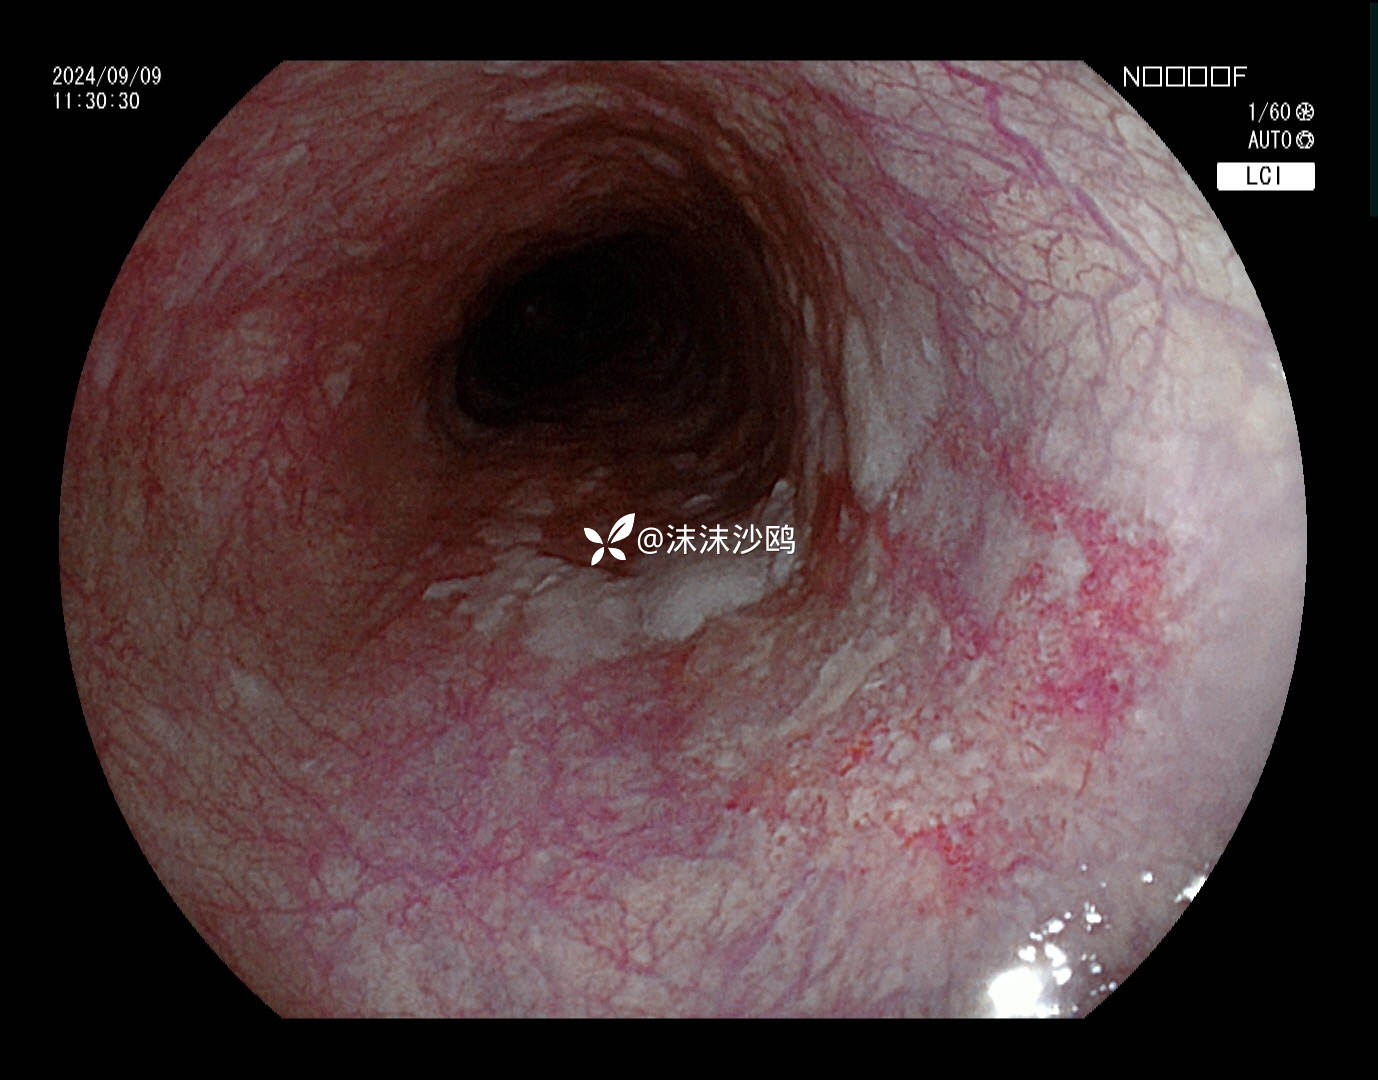

BLI

该患者平素无明显症状,吸气注气观察病灶延展性,柔软度可,白光观察粘膜呈现发红粗糙,BLI放大观察呈现明显茶褐色,可见B1型血管,局灶可见紊乱生长的B2型血管,并见AVA区域,感觉小于0.5mm。镜下考虑浸润深度,不超过SM1,应该有内镜下D的可能性。等病理结果,希望符合内镜诊断。